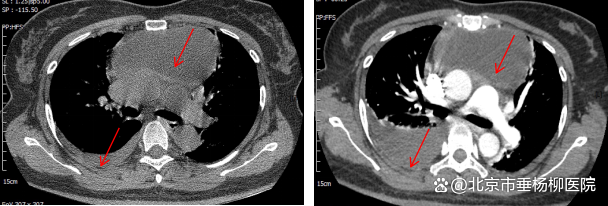

▲术前第一次胸部CT和第二次胸部增强CT

为除外其他纵膈疾病可能及全面评估病情,在急诊科的帮助下,迅速完善了胸部增强CT和心脏超声,在除外了心包脓肿和其他纵膈疾病的同时,发现了右侧胸腔积液较前明显增加,结合患者突发右侧胸痛病史,考虑纵膈感染破入右侧胸腔可能性大。